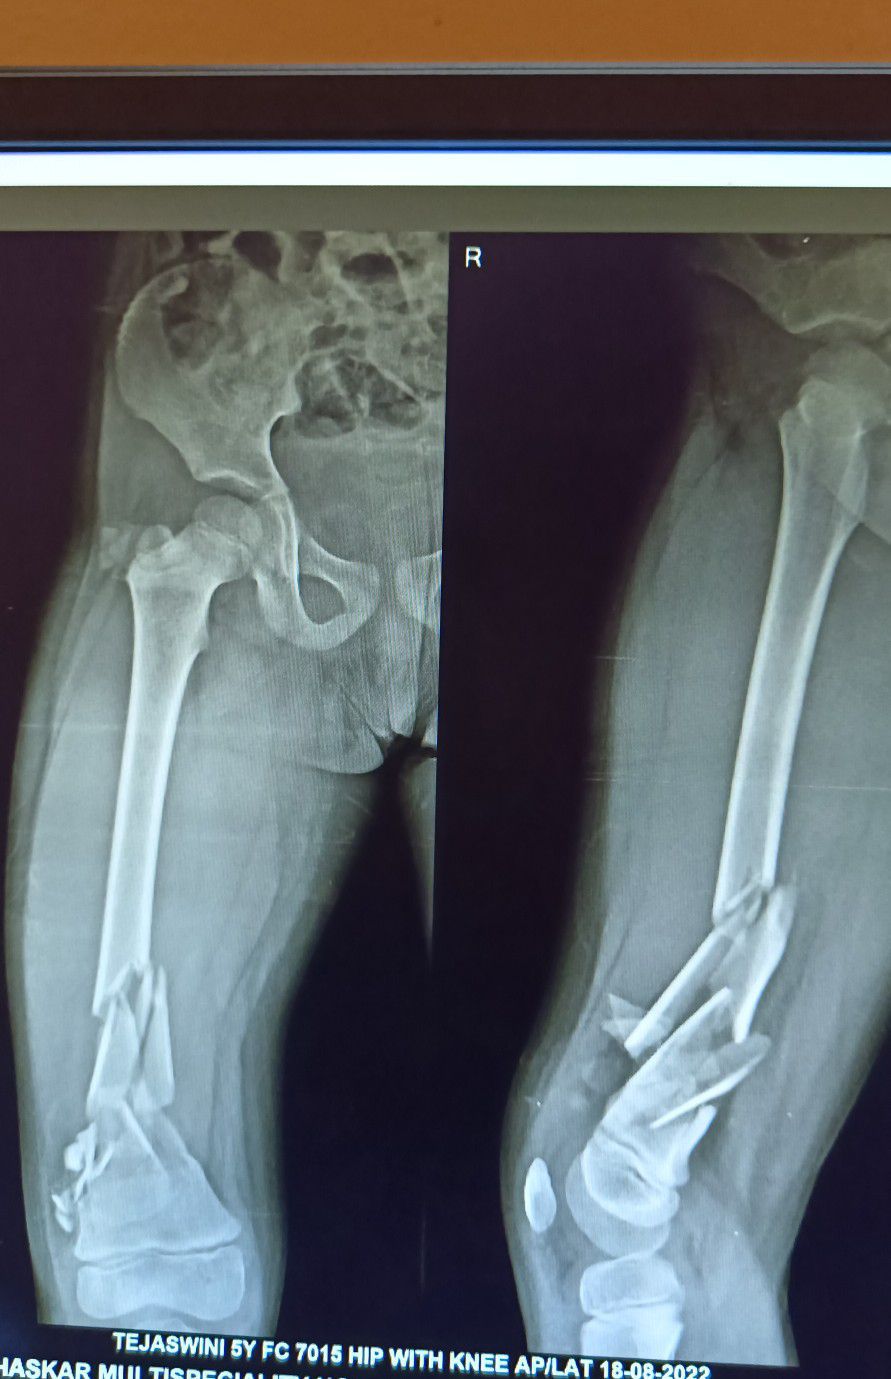

H/o RTA,Plan of Approach!

Orthopaedics

Orthopedicsurgery

Paediatric